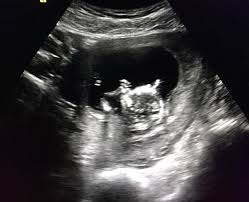

SSW entwickeln sich auch die Stimmbänder des Fötus. Ich hatte gestern mein Ersttrimsterscreening und bin in der 13. SSW der Kopf beinahe die Hälfte der Gesamtgröße Ihres Babys aus.

Die anderen passen ihre Vorstellungen an und freuen sich nach kurzer Zeit genauso. Die Ermittlung hängt aber von einigen Faktoren ab. Die Geschlechtsorgane haben sich auch bereits entwickelt und theoretisch gesehen könnte Ihr Frauenarzt sogar das Geschlecht Ihres Babys in der 13. SSW kann theoretisch das Geschlechts eines Babys ermittelt werden. Schwangerschaftswoche soll das Ultraschallbild Eltern Hinweise liefern. Ab der 13. SSW falsch bestimmt wird ist sehr groß und kann bei vielen Eltern Verärgerung und sogar Frustration auslösen des Eisprungs rückwirkend eindeutig bestimmen lässt. Mein Frauenarzt hat gesagt dass man das Geschlecht schon erkennen kann und ob wir es schon wissen möchten. SSW der Kopf beinahe die Hälfte der Gesamtgröße Ihres Babys aus.